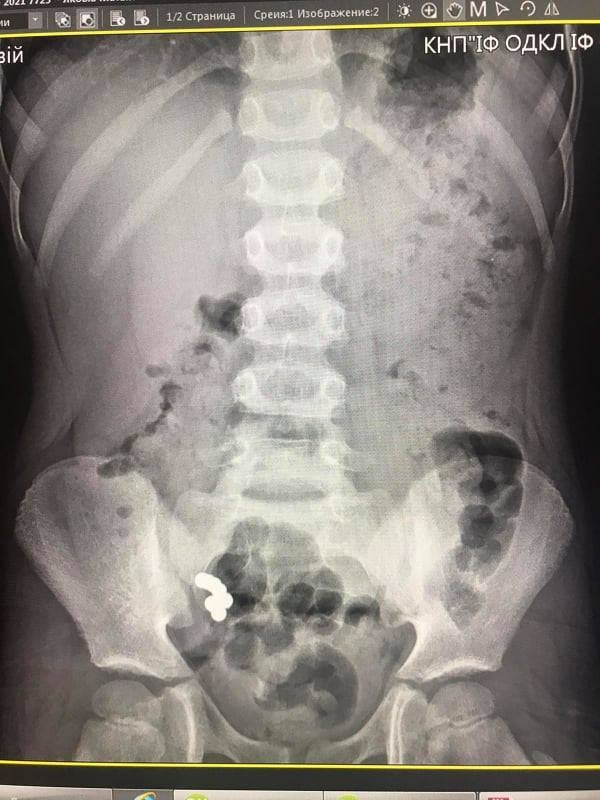

Під час рентгенологічного дослідження медики діагностували наявність магнітів в кишківнику, які не просуваються протягом 10 днів. Відсутність пасажу магнітів по кишківнику стало показанням до оперативного втручання. На операції виявили інтимне зрощення стінки тонкої кишки, де розташовані чотири магніти, зі стінкою сліпої кишки, де виявили три магніти.